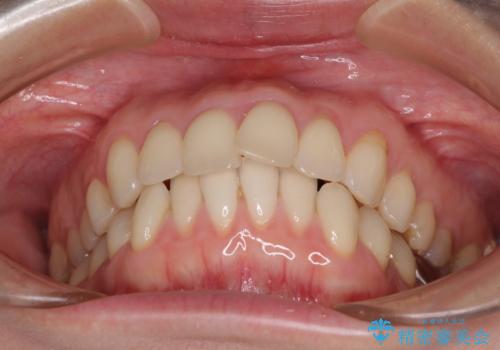

- 上下の前歯のデコボコを気にして来院された患者様です。

妊娠中であり、途中通院が難しくなる可能性があることから、インビザラインによる矯正治療を行うこととしました。

上下顎歯列全体の後方移動とIPR(歯と歯の間を削る)によってデコボコが解消するように設計しました。